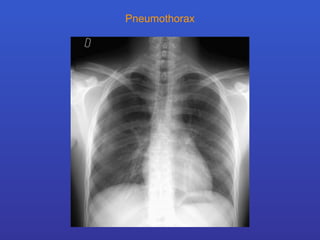

Pneumothorax